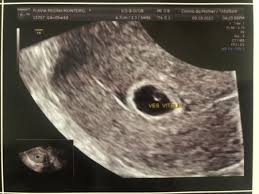

Feto Com 5 Semanas De Gestação

Semana de gestação. O embrião é do tamanho de uma semente de gergelim. A partir dessa semana o bebê passa a ganhar peso de forma mais rápida cerca de 30 a 50 g por dia.

36 a 42 dias de gestação. Me ajudem sera normal isso pra esse tempo de gestacao k tou. A 18ª a 19ª e a 20ª semanas de gravidez marcarão muitas evoluções.

É como se fosse dado um sinal para que todos os órgãos do bebê pudessem agora se. Os sintomas de azia sensação de queimação no. O que muda no teu corpo nas 5 semanas de gravidez. Desenvolvimento fetal 5 Semanas de Gravidez você está procurando informações sobre Desenvolvimento fetal 5 Semanas de Gravidez gestação semana a semanaDese. Embora você provavelmente já tenha engordado entre 2 e 5 quilos o feto não pesa mais que 70 gramas. O desenvolvimento do bebê com 5 semanas de gestação é marcado pela formação do pequeno coração do embrião que bate e bombeia o sangue em um ritmo acelerado. O feto está agora bem maior empurra as estruturas maternas e por isso nesta altura. O cabelo da cabeça cresce mais e as pálpebras abrem. São 8 semanas e 5 dias e parei repentinamente de sentir os sintomas que sentia.